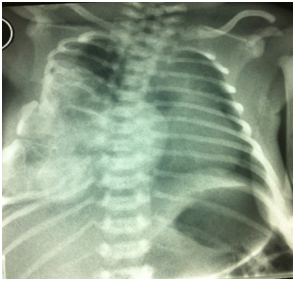

Follow-up MRI of the thorax performed two months later did not reveal any relapse of the mass. Thoracic scoliosis was seen on the AP plain film of the spine on the 4-month follow-up. The paradoxical respiration has resolved Figure 5. On the 6th month follow-up an appropriate scoliosis bandage was prescribed by the orthopedic surgeon Figure 6. Currently the baby is on orthopedic follow up for her scoliosis repair.

Figure 5 Plain radiogram 2 months later. Note the ipsilateral scoliosis.

Figure 6 Plain radiogram 6 months later. The vertebral column is supported by appropriate bandage.